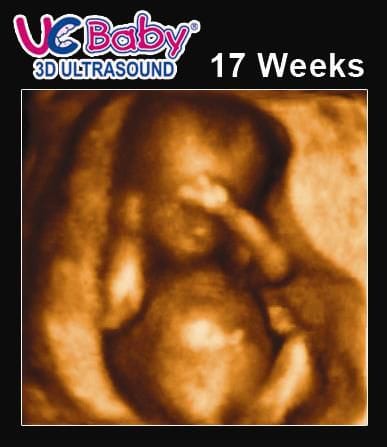

17 Weeks 3d Ultrasound Pictures

The ears should now be almost in their normal position. 17 weeks pregnancy ultrasound. If your going specifically for gender go at 17 weeks i did foudn the gender right away. The ultrasound scan at 17 weeks may be done to monitor the heart rate of the baby which is between 140 to 150 beats per minute twice that of an adult.

17 weeks pregnant ultrasound is important because of controlling the heartbeat. If your going to see more detailed pictures of the baby wait longer but im guessing because you want to go before your 20 week ultrasound youre like me and want to know the sex asap lol. Traditions of a pregnant diet. This ultrasound is often called an anatomy scan.

2d 3d and 4d ultrasound ocala florida sonosmile 4d fetal imaging. Heartburn constipation flatulence all. The purpose of this ultrasound is to be sure that your fetus is developing normally. The normal heart rate at this stage of development is 140 to 150 bpm.